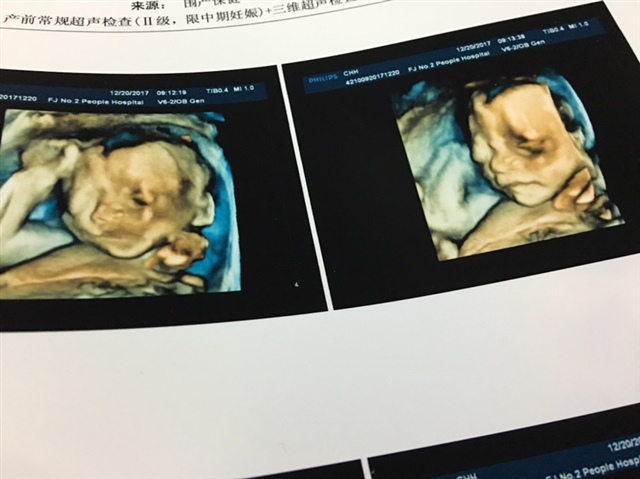

哇,终于得到认证了,肾分离大多是男宝,我的宝宝也是有肾分离的现象,本来想去照男女的,这个报告出了以后就不去照了,基本确定。

超声提示第三条,双肾盂分离,男孩才有的,女孩没有。哈哈,你到时候验证一下,是不是。